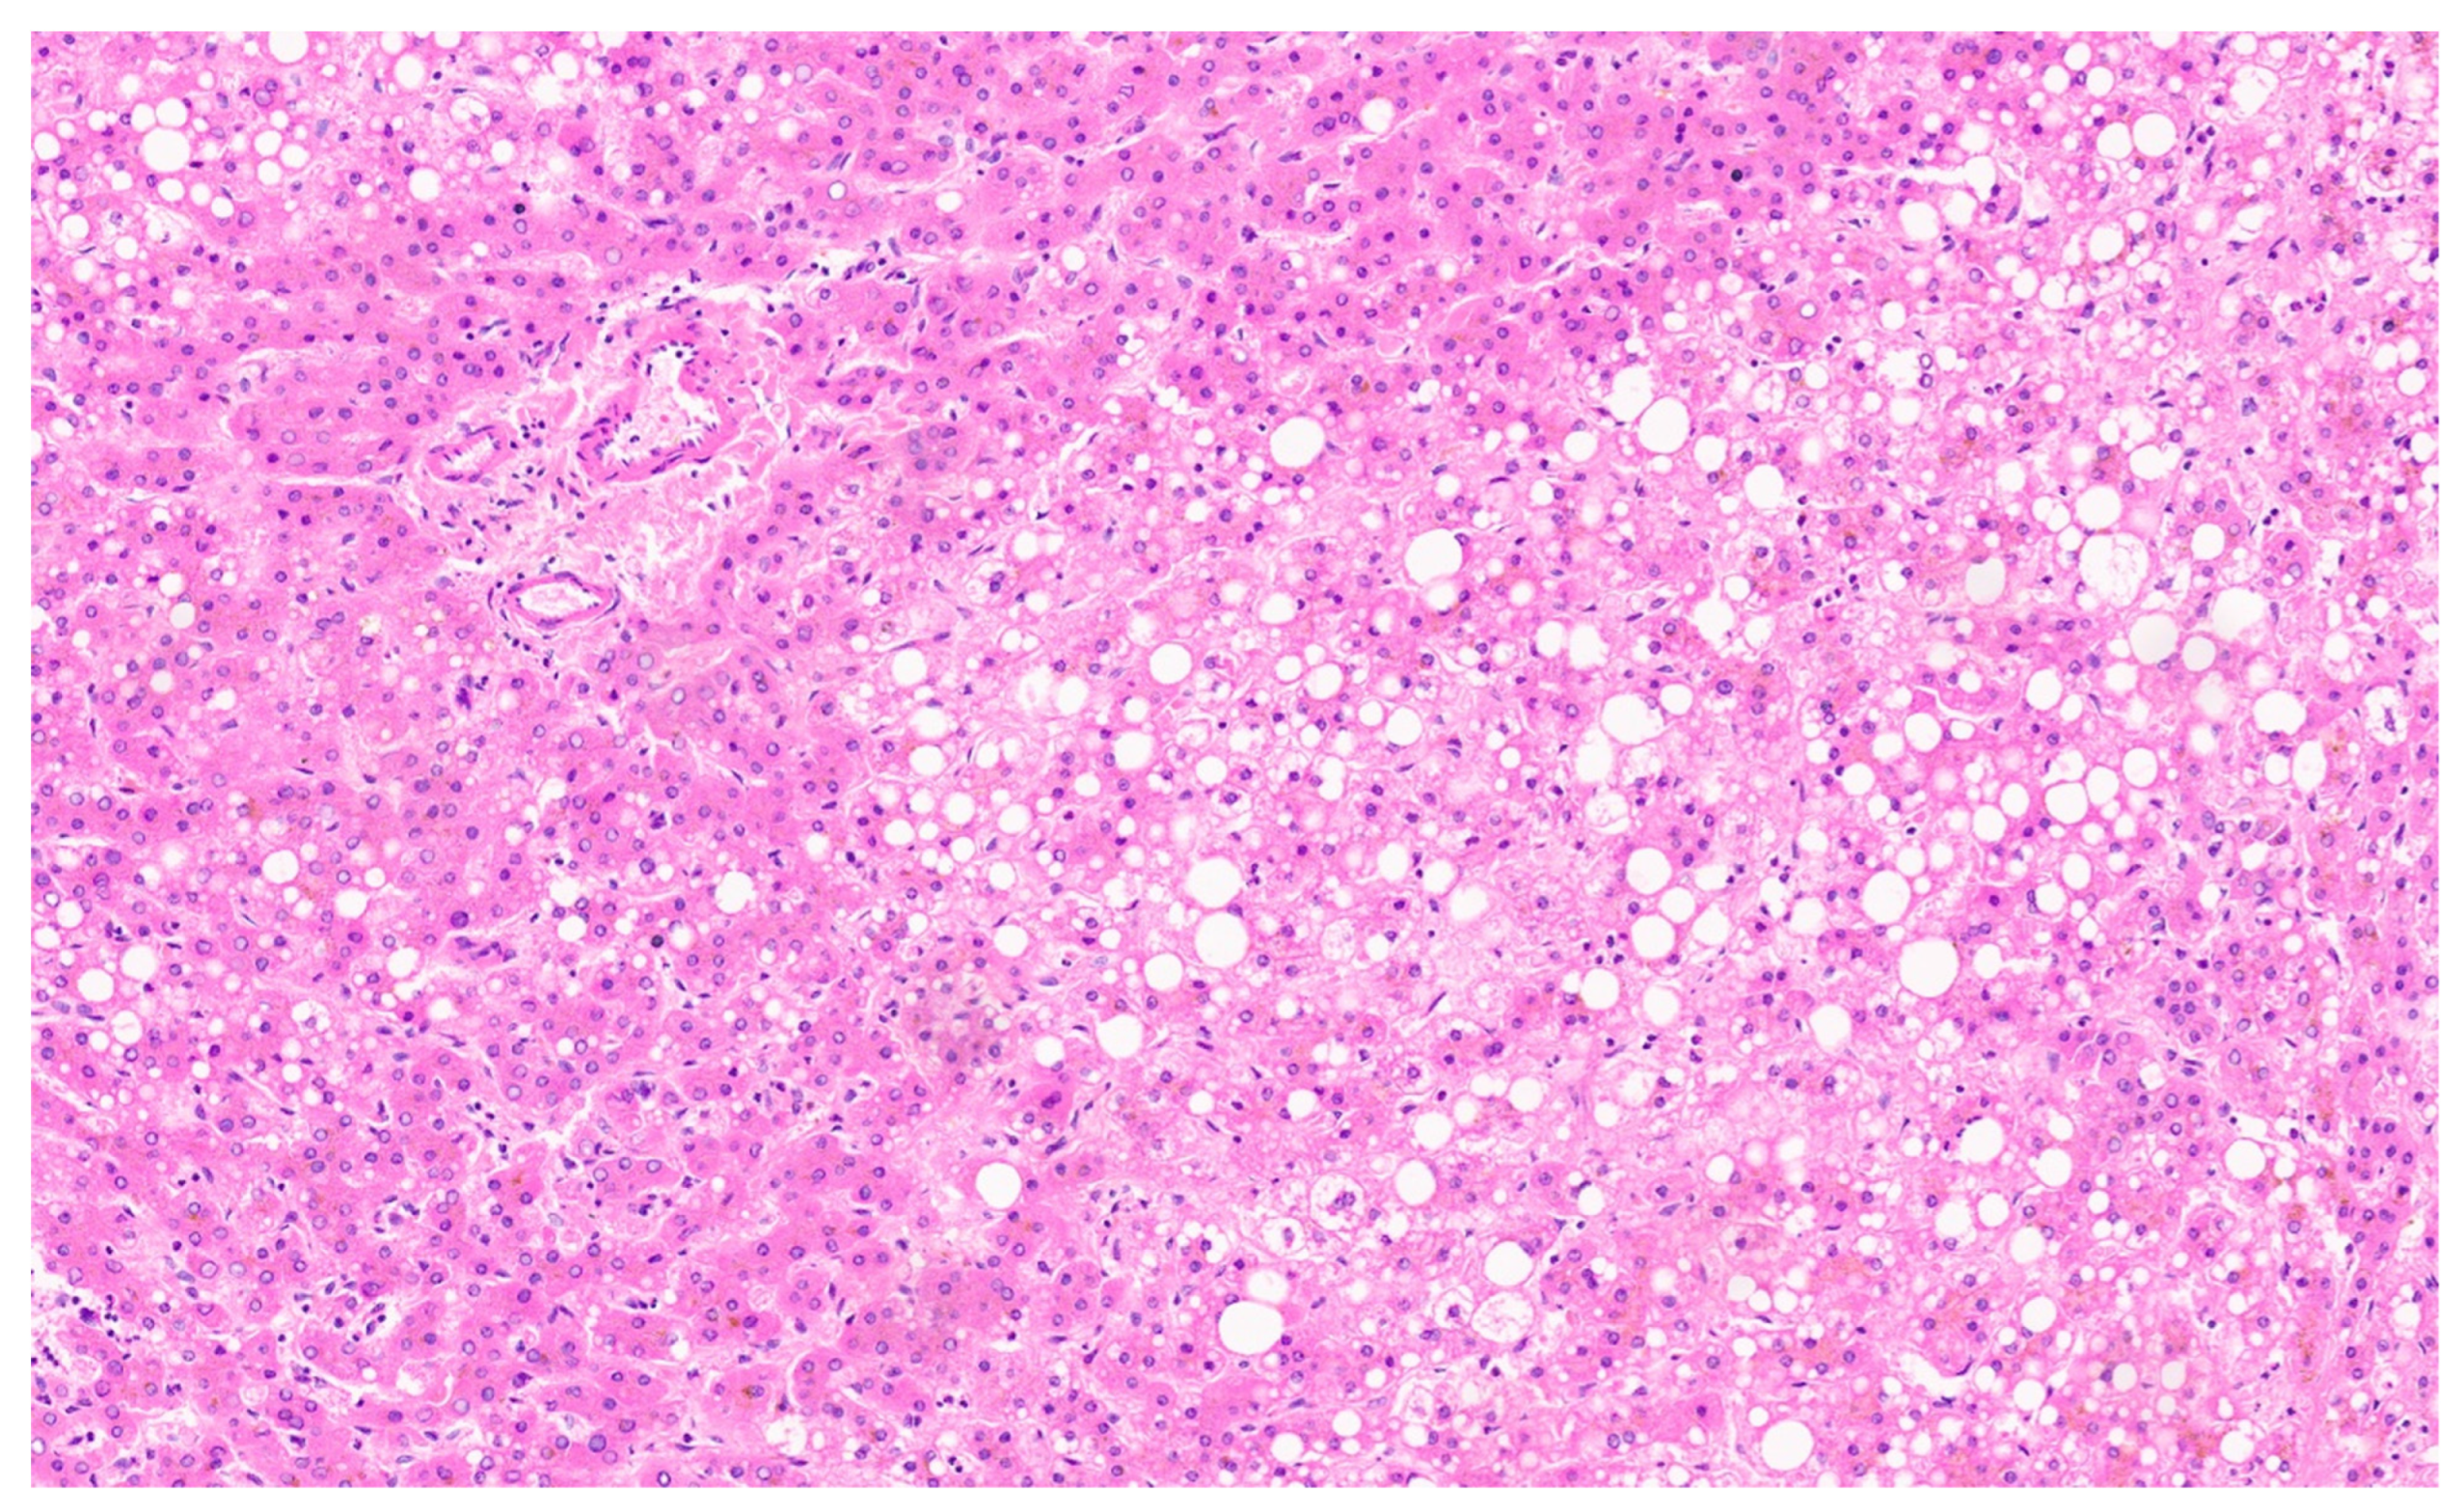

13.4. Pathology